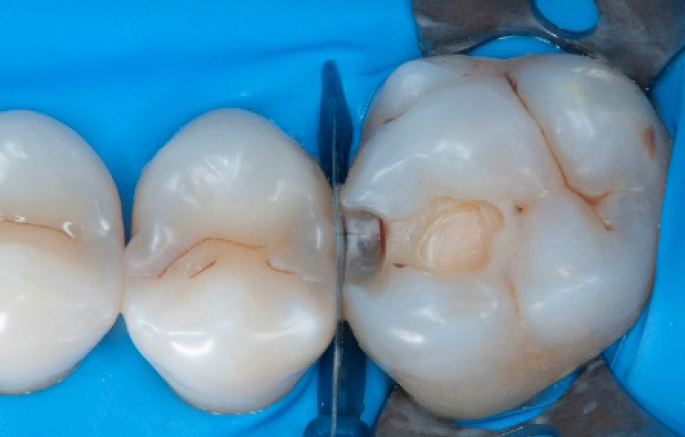

Step 2:

Initial cavity preparation, protecting the adjacent tooth with a Palodent1 WedgeGuard.

Step 3:

Class II cavity prepared.